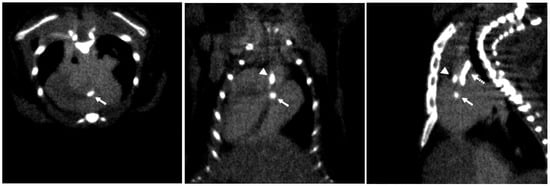

- Andelovic, K.; Winter, P.; Jakob, P.M.; Bauer, W.R.; Herold, V.; Zernecke, A. Evaluation of Plaque Characteristics and Inflammation Using Magnetic Resonance Imaging. Biomedicines 2021, 9, 185. [Google Scholar] [CrossRef]

- Hur, J.; Park, J.; Kim, Y.J.; Lee, H.J.; Shim, H.S.; Choe, K.O.; Choi, B.W. Use of contrast enhancement and high-resolution 3D black-blood MRI to identify inflammation in atherosclerosis. JACC-Cardiovasc. Imaging 2010, 3, 1127–1135. [Google Scholar] [CrossRef]

- Segers, F.; Ruder, A.V.; Westra, M.M.; Lammers, T.; Dadfar, S.M.; Roemhild, K.; Lam, T.S.; Kooi, M.E.; Cleutjens, K.; Verheyen, F.K.; et al. Magnetic resonance imaging contrast-enhancement with superparamagnetic iron oxide nanoparticles amplifies macrophage foam cell apoptosis in human and murine atherosclerosis. Cardiovasc. Res. 2023, 118, 3346–3359. [Google Scholar] [CrossRef]

- Reimann, C.; Brangsch, J.; Kaufmann, J.O.; Adams, L.C.; Onthank, D.C.; Thone-Reineke, C.; Robinson, S.P.; Hamm, B.; Botnar, R.M.; Makowski, M.R. Dual-probe molecular MRI for the in vivo characterization of atherosclerosis in a mouse model: Simultaneous assessment of plaque inflammation and extracellular-matrix remodeling. Sci. Rep. 2019, 9, 13827. [Google Scholar] [CrossRef]